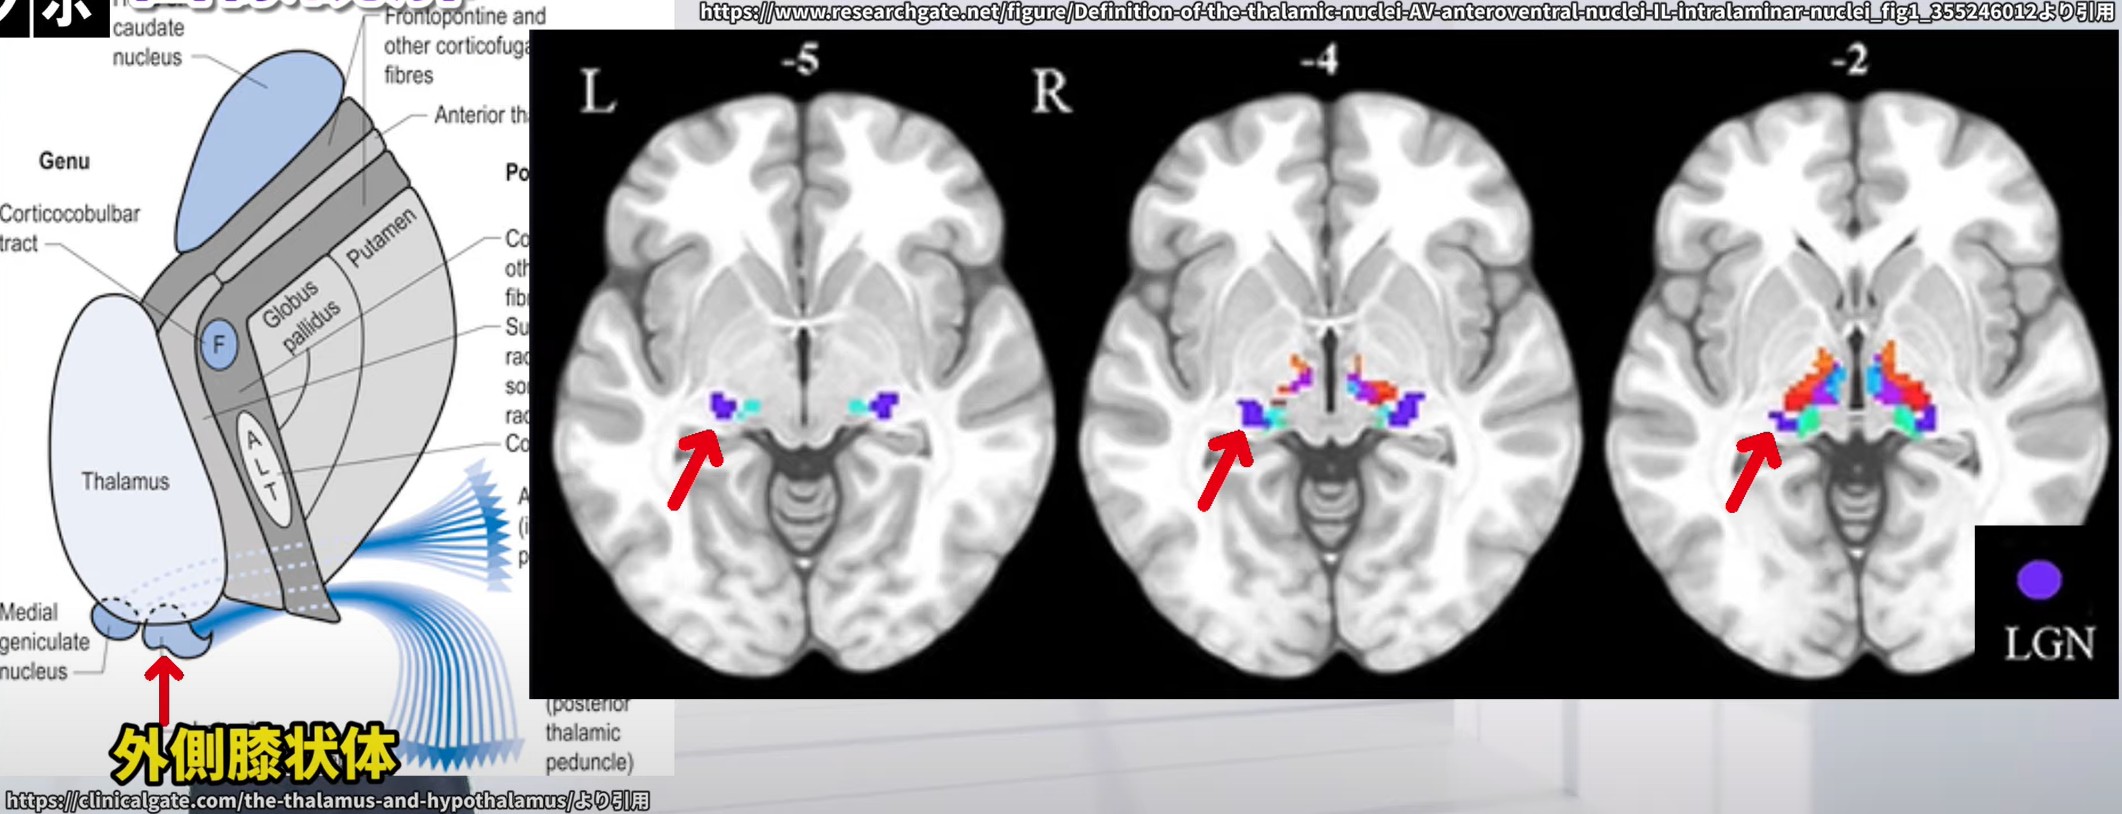

視床外側膝状体(lateral geniculate nucleus, LGN)は、視床の後部・腹側に位置する小型の神経核で、内側膝状体(medial geniculate nucleus)の外側に隣接しています。MRI上では、視床の後方部、第3脳室の外側に沿った三日月形の構造として観察されます。特に内包後脚や海馬といったランドマークとの位置関係からも同定が可能です。

画像読解のポイント

① 視床の位置確認

LGNは視床内に位置するため、まず視床そのものをランドマークとして同定することが重要です。

軸方向(アキシャル)MRIスライスで、第3脳室の両側にある大きな卵型の構造を探します。視床は多数の神経経路が集まるハブとして機能しており、視床後部にLGNが存在します。

② 後面への注目

LGNは視床の**後部(posterior)**に位置しています。

そのため、視床後方のスライスに注目して画像を確認することが、LGNを見つけるための有効なアプローチとなります。

③ 形状とサイズ

LGNは非常に小さく、膝のように曲がった形または三日月型として知られています。

視床全体に比べるとサイズが小さいため、画像の拡大やズーム機能を活用することで識別しやすくなります。

⑦ 機能的イメージングの活用

**fMRI(機能的MRI)や拡散テンソル画像(DTI)**では、LGNを含む視覚経路の活動部位や神経線維束の走行を可視化できます。

視覚刺激に対するLGNの反応や、視放線の構造的評価において非常に有用です。